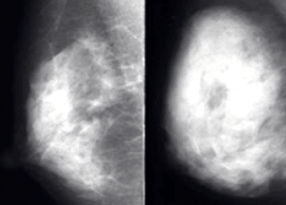

치밀유방은 유방 내 지방조직보다 유선조직과 결합조직의 비율이 높아 유방의 밀도가 높은 상태를 말합니다. 쉽게 말해 유방 내부에 실질 조직(유선과 결합조직)이 많고 지방 조직이 적은 상태입니다. 유방 밀도는 유방촬영술(맘모그래피)을 통해 확인할 수 있으며, 일반적으로 4단계로 분류됩니다.

둘째, 치밀유방은 유방촬영술에서 유방 조직과 종양이 모두 하얗게 보여 암을 발견하기 어렵게 만듭니다. 이로 인해 조기 발견이 지연되어 예후가 나빠질 수 있습니다. 특히 고도 치밀유방(유방 밀도 75% 이상)의 경우 유방암 진단 확률이 크게 증가하므로 정기적인 검진과 조기진단이 필수적입니다.

치밀유방은 유방촬영술(맘모그래피)만으로는 종양이나 미세석회화 등 초기 암 징후를 발견하기 어렵습니다. 유방 실질 조직과 종양이 모두 하얗게 보이기 때문에 마치 '하얀 배경에 하얀 눈을 찾는 것'과 같은 어려움이 있습니다. 이러한 이유로 치밀유방을 가진 여성들에게는 더욱 철저한 검진과 다양한 검사법의 병행이 필요합니다.

하지만 치밀유방에서는 정상 조직과 종양의 구분이 어려워 한계가 있습니다. 치밀유방에서의 유방촬영술 민감도는 약 30~48%로 낮아, 추가적인 검사가 필요한 경우가 많습니다.